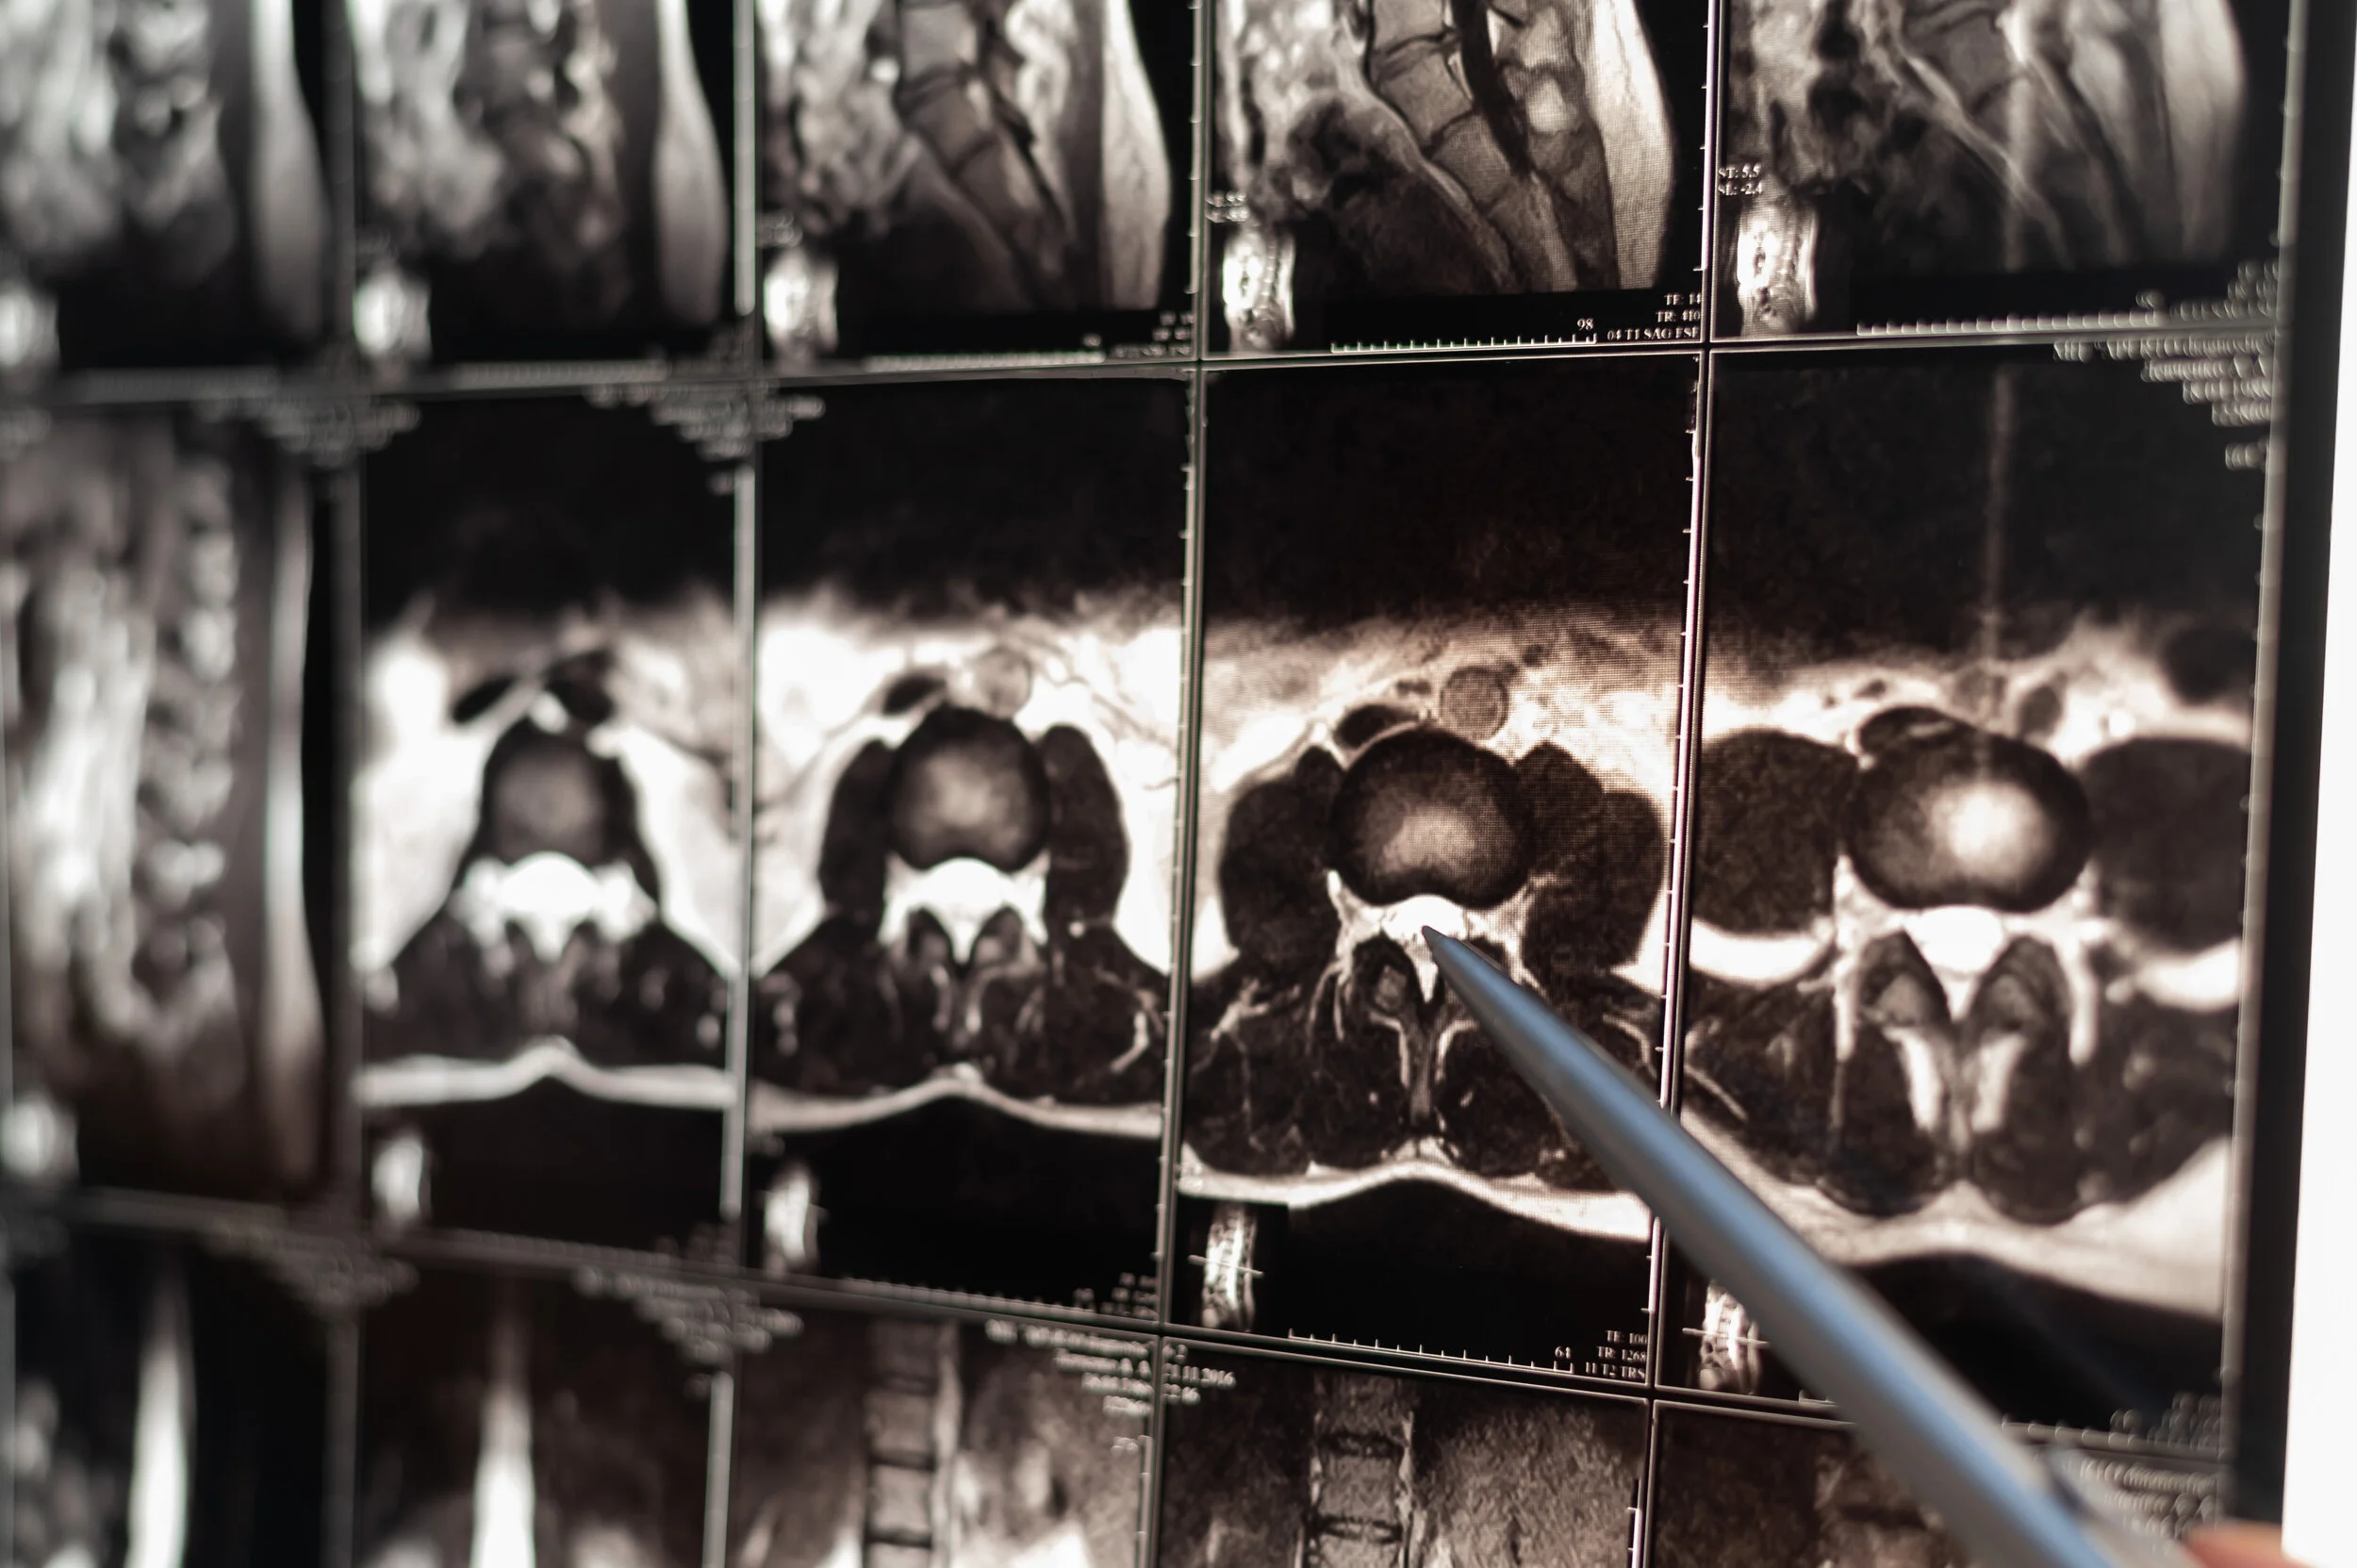

We review and dictate the imaging study as if reading it for the first time. This report will be clear and concise using definitive terms describing each anatomic structure in detail and, when appropriate, using specific measurements with objective terminology.